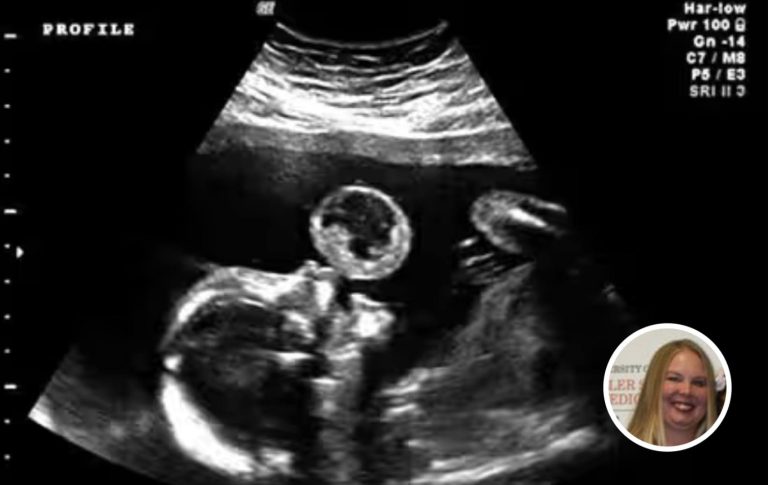

Hearing that, I felt a twinge of hope, though I tried not to get ahead of myself. I tried to focus on what was happening day to day: the gentle kicks in my belly, the way Jalen would lay his ear against my stomach and talk softly to our child, the small but vital joys we shared as we prepared for this new chapter.

A few weeks later, I gave birth to a baby girl. Jalen was by my side the entire time, his eyes misty with both awe and exhaustion. When she came into the world, I felt a rush of emotion I can’t even put into words. We named her Marisol, a name that felt radiant and full of hope.